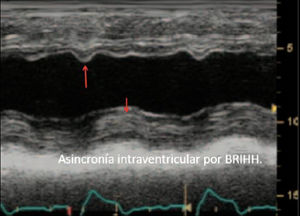

| Para una adecuada valoración de la función regional se exige una buena definición endocárdica, la visualización de todas las paredes en los diversos cortes y la confirmación de que las alteraciones segmentarias vistas en un corte se confirman en otra proyección distinta. Situaciones en que la motilidad anormal se acompaña de un engrosamiento normal (bloqueo de rama izquierda, ritmo de marcapasos, poscirugía cardiaca, constricción pericárdica) deben distinguirse de las alteraciones isquémicas, en las que la motilidad anormal se acompaña de alteraciones en el engrosamiento miocárdico. | ||

Cuando existen dificultades para objetivar cuantitativamente la FEVI, la estimación visual constituye el método más utilizado en la valoración de la función sistólica. Si bien este método, en el caso de observadores expertos, tiene aceptable correlación con la determinada por ventriculografía, su precisión disminuye con la menor experiencia y, en el caso de ventrículos de morfología anormal, con contracción no homogénea, alteraciones segmentarias de la contractilidad o en presencia de asincronía15.